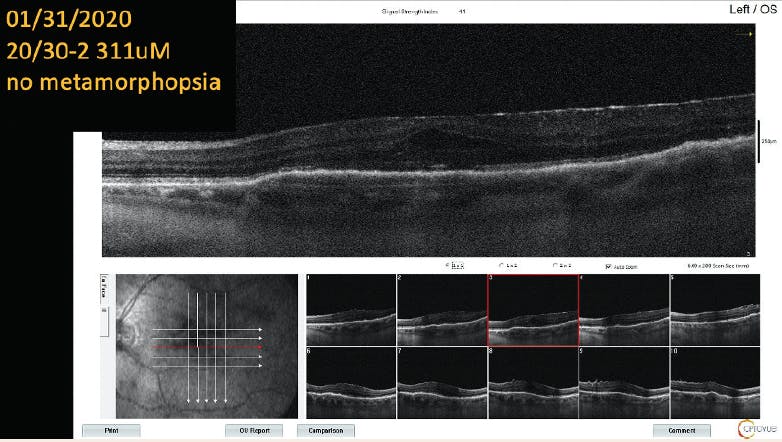

Case 3: PED, Metamorphopsia, and Wet AMD

By Nikolas J.S. London, MD, FACS

Patient History:

• 70-year-old white man who lives 4 hours from the office

• Patient presented with 20/40 VA OS. Significant, symptomatic metamorphopsia was noted, associated with a large pigment epithelial detachment (PED; Figure 1).

<p>Figure 1. The patient presented with 20/40 VA, metamorphopsia, and a PED.</p>

Click to view larger

Figure 1. The patient presented with 20/40 VA, metamorphopsia, and a PED.

Intervention:

• Monthly ranibizumab (Lucentis, Genentech) therapy was initiated. No significant changes were observed after four doses.

• At month 5, bevacizumab (Avastin, Genentech) was delivered. No change was observed after therapy.

• Aflibercept (Eylea, Regeneron) was administered during six monthly visits. No change was observed (Figure 2).

• After a discussion with the patient about treatment options, brolucizumab (Beovu, Novartis) therapy was initiated.

• After two monthly doses, the patient’s anatomy and metamorphopsia resolved, and VA was 20/30 (Figure 3). The patient was ecstatic about his vision and insisted on continuing brolucizumab therapy despite new safety concerns.

• For the past 6 months, the patient has visited the office every 8 weeks for brolucizumab therapy. Visual acuity and symptoms remain stable. However, he appears to be developing recurrent PED and subretinal fluid at the 8-week interval, and we will need to explore other options going forward. He has received seven injections of brolucizumab.

<p>Figure 2. After 11 monthly doses of various anti-VEGF agents, the patient’s condition remained largely unchanged.</p>

Figure 2. After 11 monthly doses of various anti-VEGF agents, the patient’s condition remained largely unchanged.

<p>Figure 3. After two injections of brolucizumab, the patient’s PED resolved, and VA improved to 20/30.</p>

Figure 3. After two injections of brolucizumab, the patient’s PED resolved, and VA improved to 20/30.